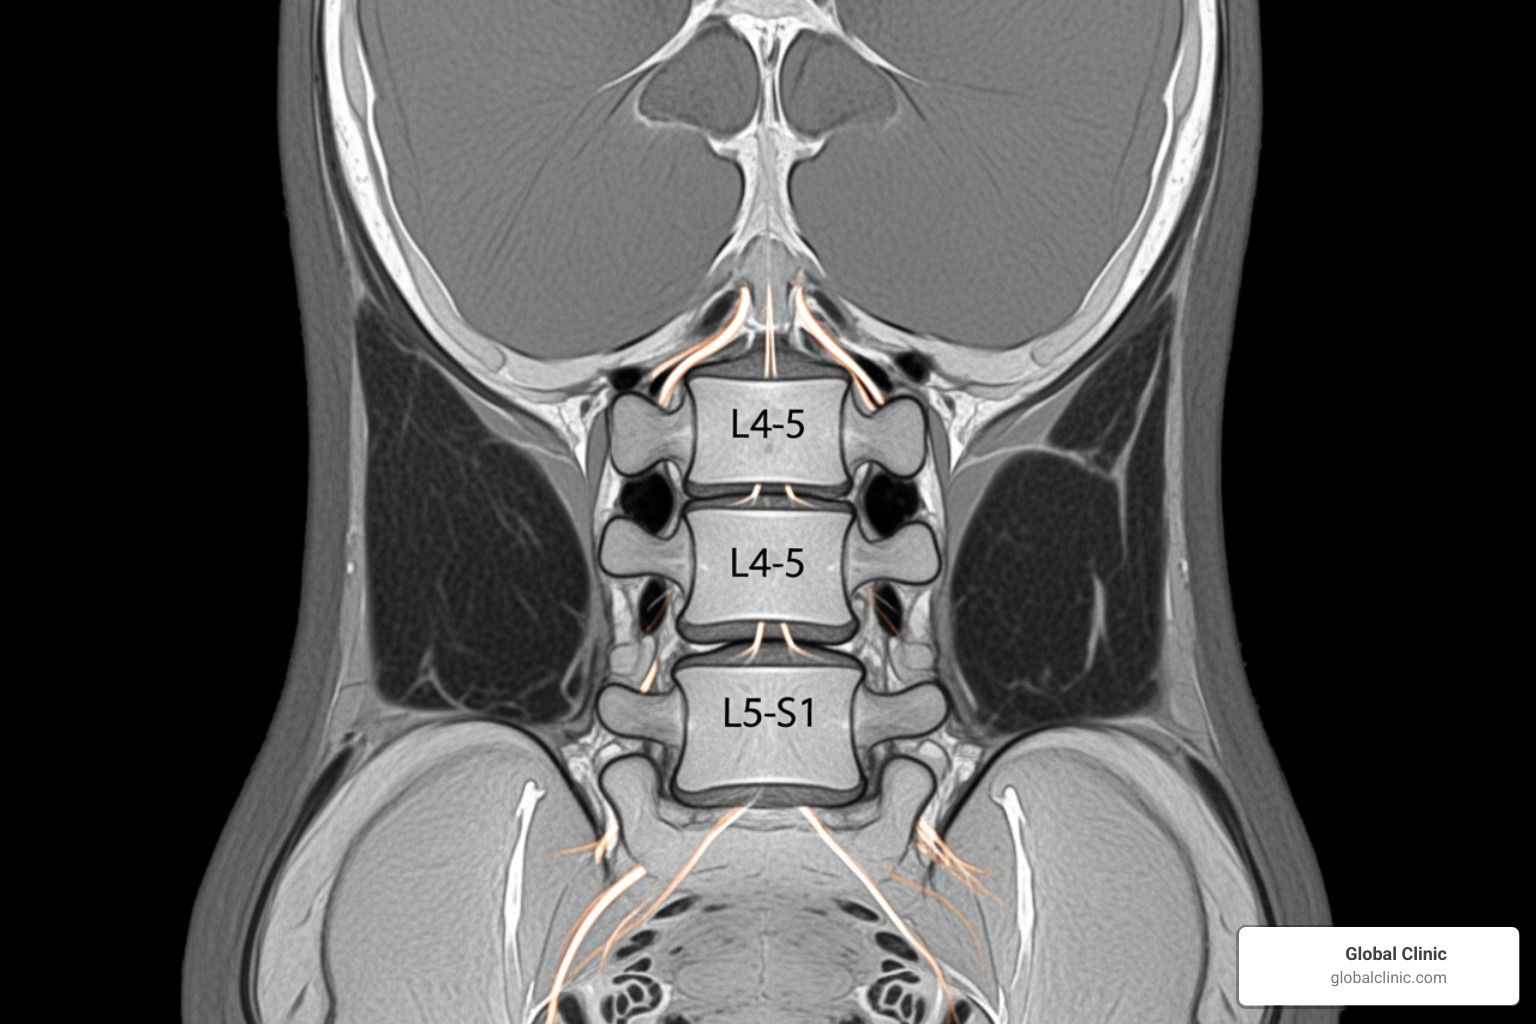

To get a clear picture of your spine, we often use diagnostic imaging. MRI scans show soft tissues like discs and nerves in detail, while CT scans are excellent for viewing bone structures. These tools help us confirm if a condition like a herniated disc or spinal stenosis is causing your symptoms, ensuring we recommend the right treatment.

Diagnosis starts with a detailed history and physical exam (range of motion, strength, reflexes, sensation). Imaging clarifies the cause: MRI for discs and nerves, CT for bone detail, and X-rays for alignment/degeneration. Electromyography (EMG) may help confirm which nerve roots are affected.